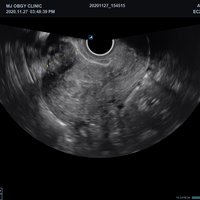

Endokavitär-Sonden

• VE3-10H (3-10 MHz) für Ultraschalluntersuchungen in Bereichen Geburtshilfe,

• Gynäkologie, Urologie, EM

• EV2-11H (2-11 MHz) für Ultraschalluntersuchungen in Bereichen Geburtshilfe,

• EC2-11H (2-11 MHz) für Ultraschalluntersuchungen in Bereichen Geburtshilfe,